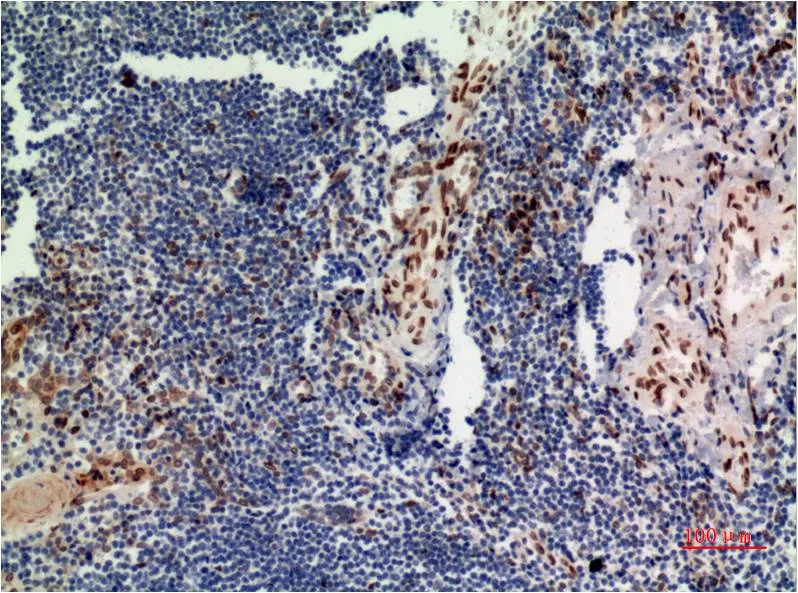

JAK2 (6B4) Mouse Monoclonal Antibody

Cat: AMM00767

Size1:50μL Price1:$150

Size2:100μL Price1:$280

Size3:500μL Price1:$280

Application:IHC-P

Reactivity:Human,Rat,Mouse

Conjugate:Unconjugated

Gene Name:JAK2